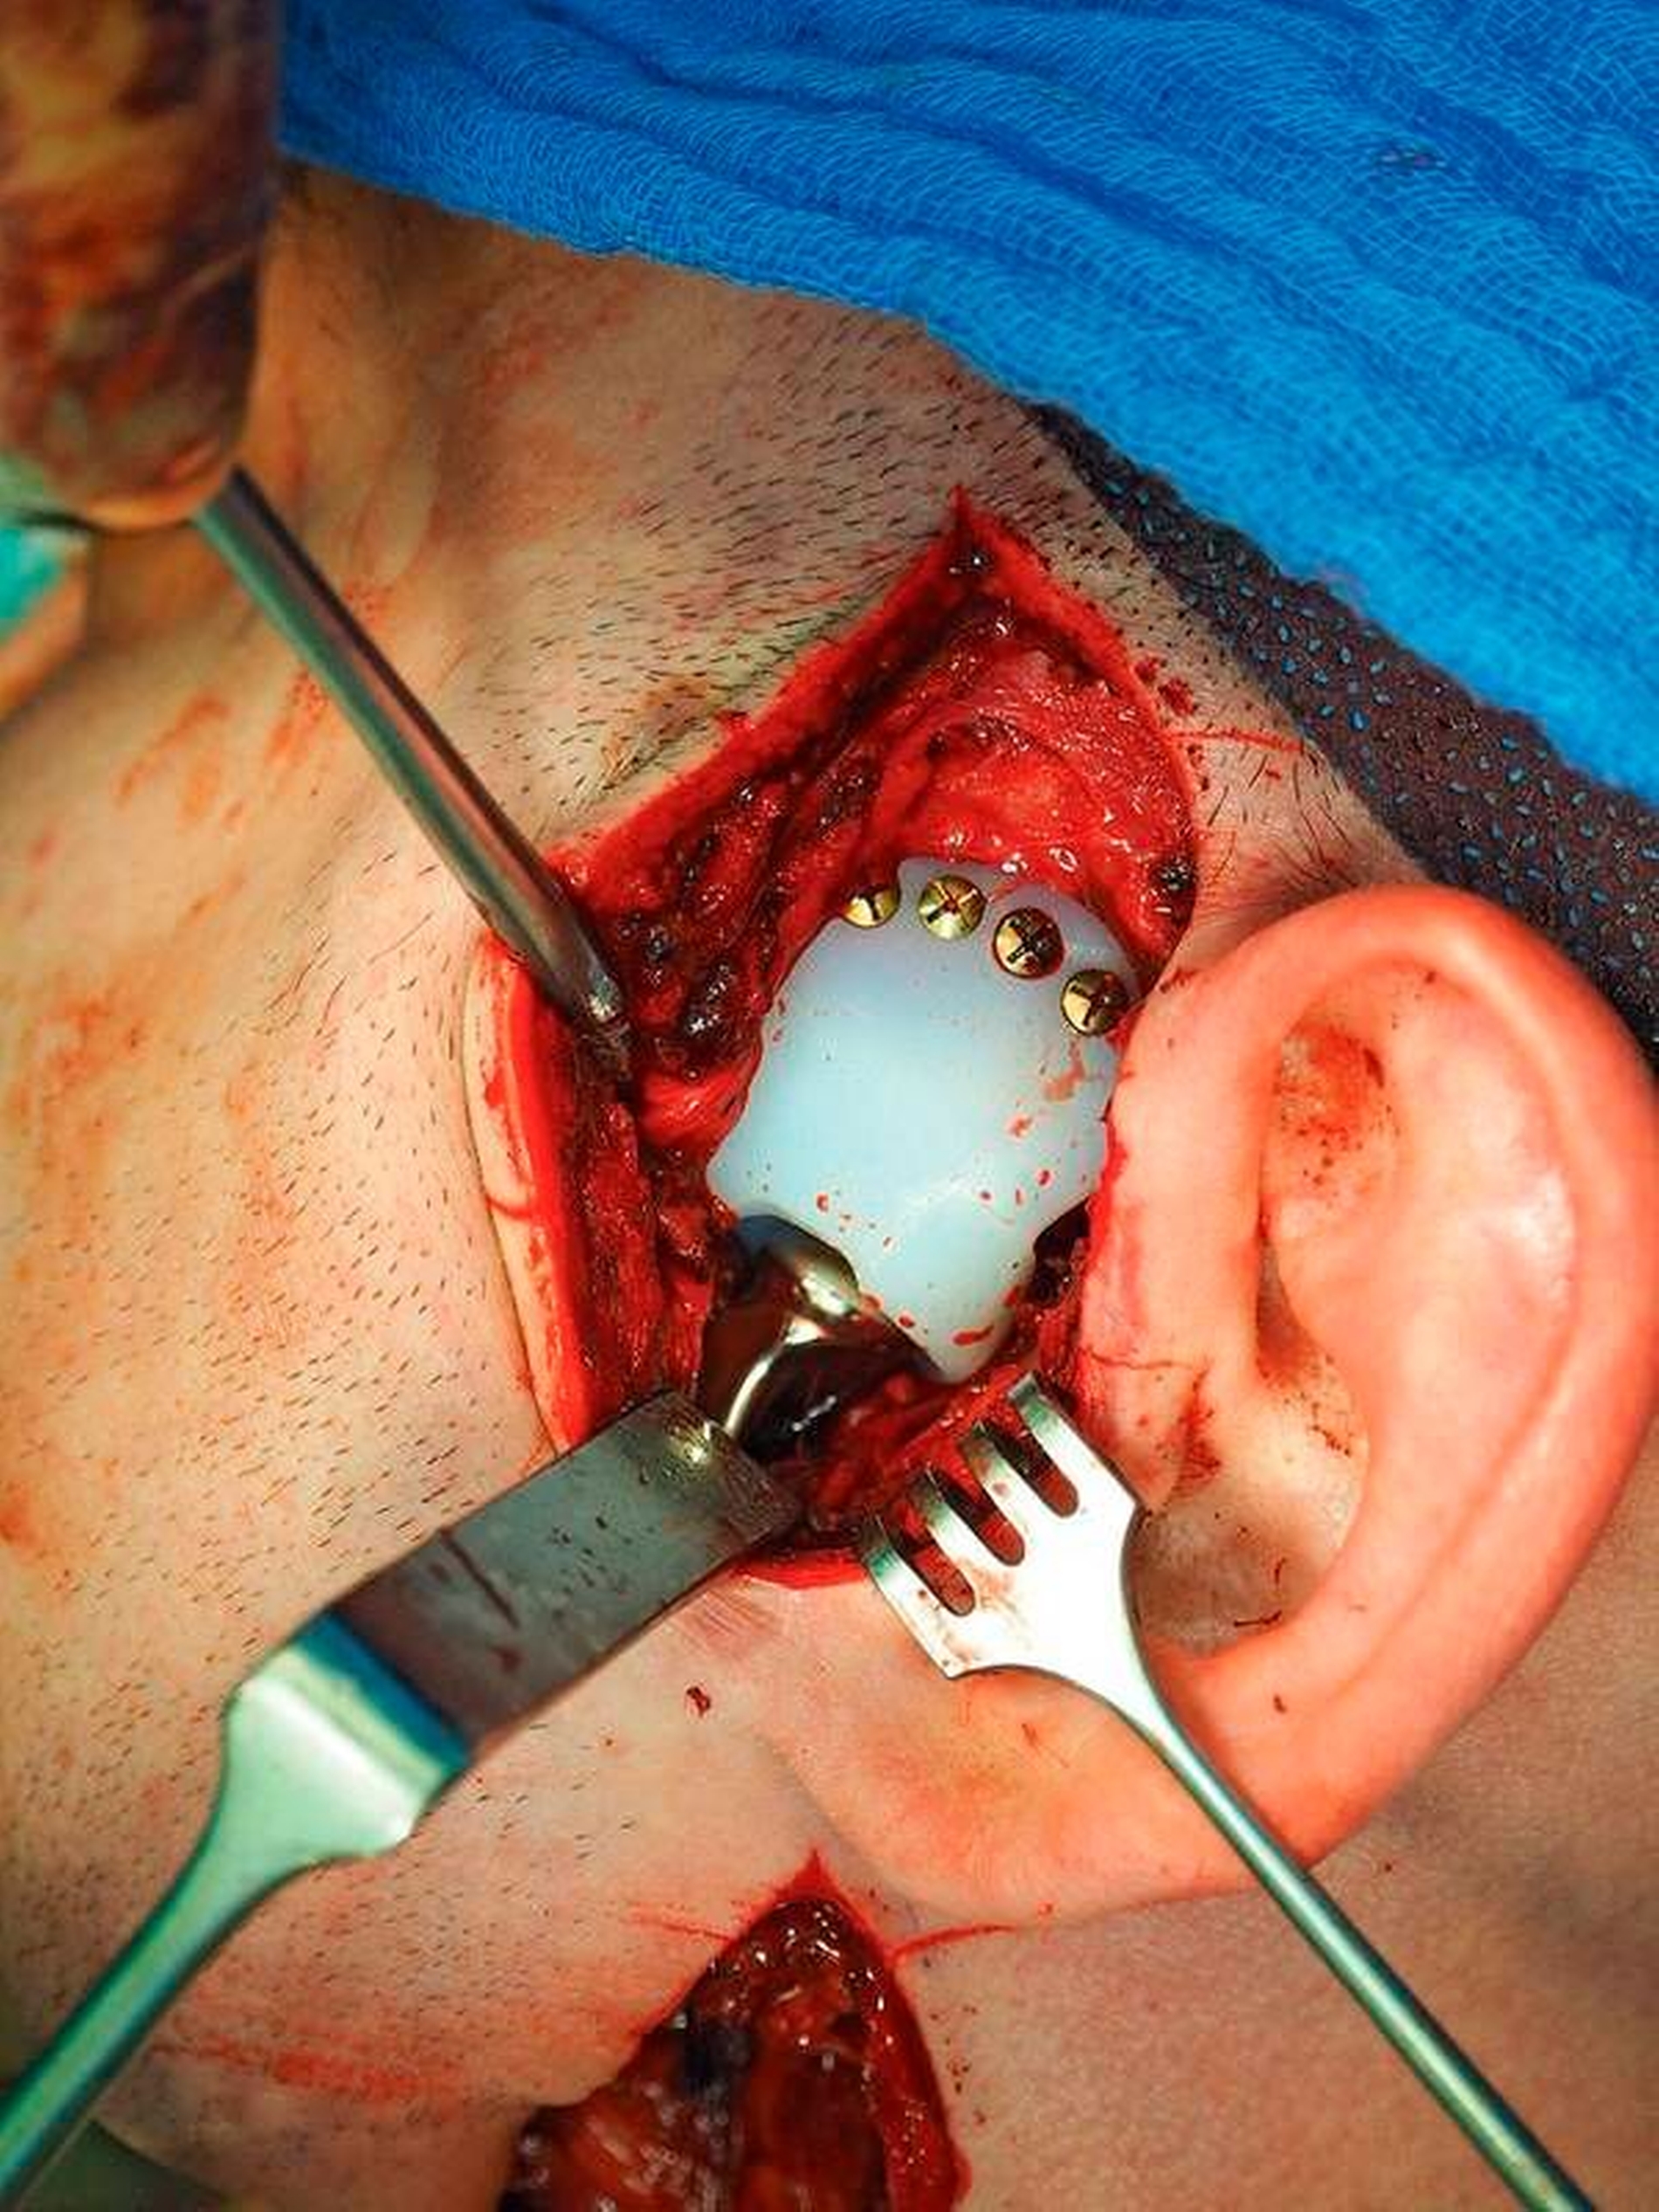

Vorgeschlagen wurde dem Patienten der totale Gelenkersatz beidseits – mit auf Basis der CT-Daten individuell erstellten Fossa-Komponenten aus einem speziellen Kunststoff (Ultra High Molecular Weight Polyethylene) und individuellen Gelenkkopfprothesen aus einer titanbeschichteten Chrom-Kobalt-Legierung (Biomet Microfixation Inc., Vertrieb Zimmer Biomet Deutschland GmbH). Der Patient und seine Angehörigen wurden in intensiven Gesprächen über die Vorteile und Risiken des Eingriffs aufgeklärt.

Nach Akzeptanz des Behandlungsplans wurden die TEPs (Totalendoprothesen) beidseits über jeweils einen präaurikulären und einen retromandibulären Zugang implantiert. Diese Prothesen wurden mit Schrauben – mit exakt am CT-Datensatz definierten Schraubenlängen – fixiert. Bei der Planung der Schraubenpositionierung wurde der Verlauf des N. alveolaris inferior berücksichtigt und der Nerv geschont.

Vor der definitiven Fixierung der Prothesen wurden Dummys als Test eingesetzt, um eine optimale Positionierung der passgenauen finalen Prothesen zu erreichen (Abbildung 2 bis 9). Abbildung 10a und 10b zeigen die postoperative Röntgenkontrolle.